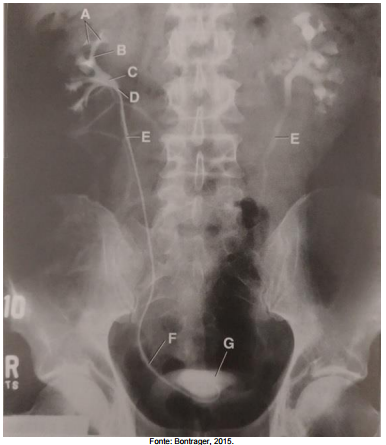

Assinale a alternativa que apresenta a correta correlação entre a indicação e a estrutura na imagem tomográfica.